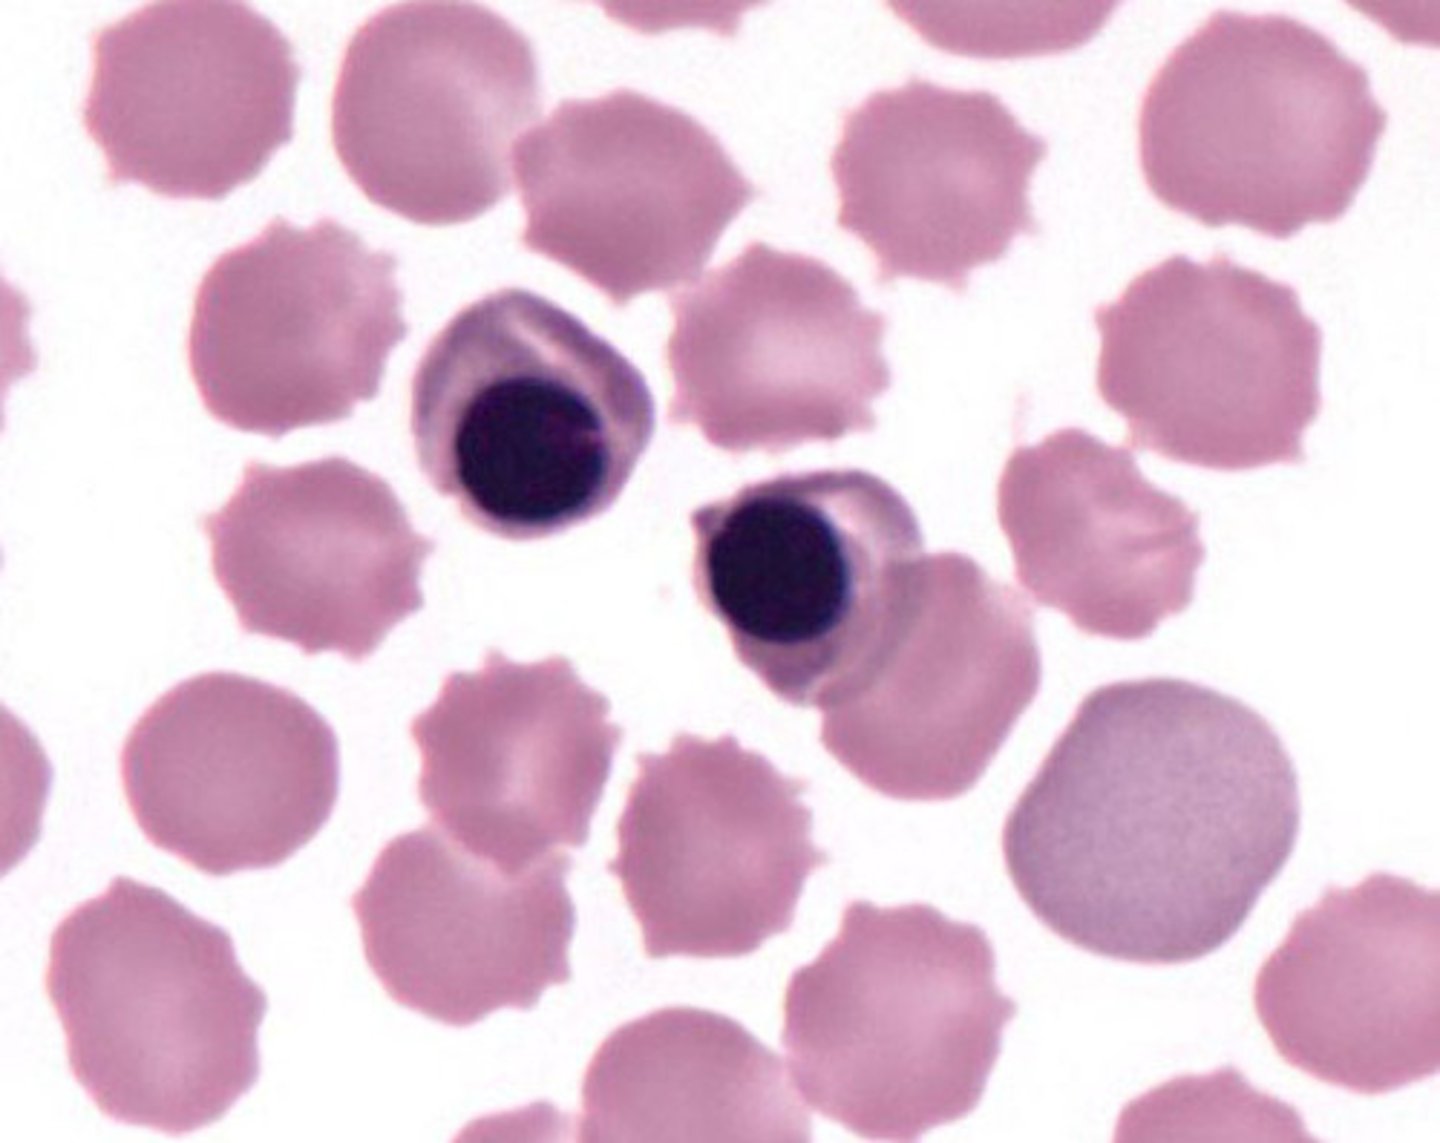

toxic neutrophils

MAMMAL

1. increase basophilia in cytoplasm

2. dohle bodies

3. vacuolated/foamy cytoplasm

4. +/- increase in cell size

dohle bodies

MAMMAL